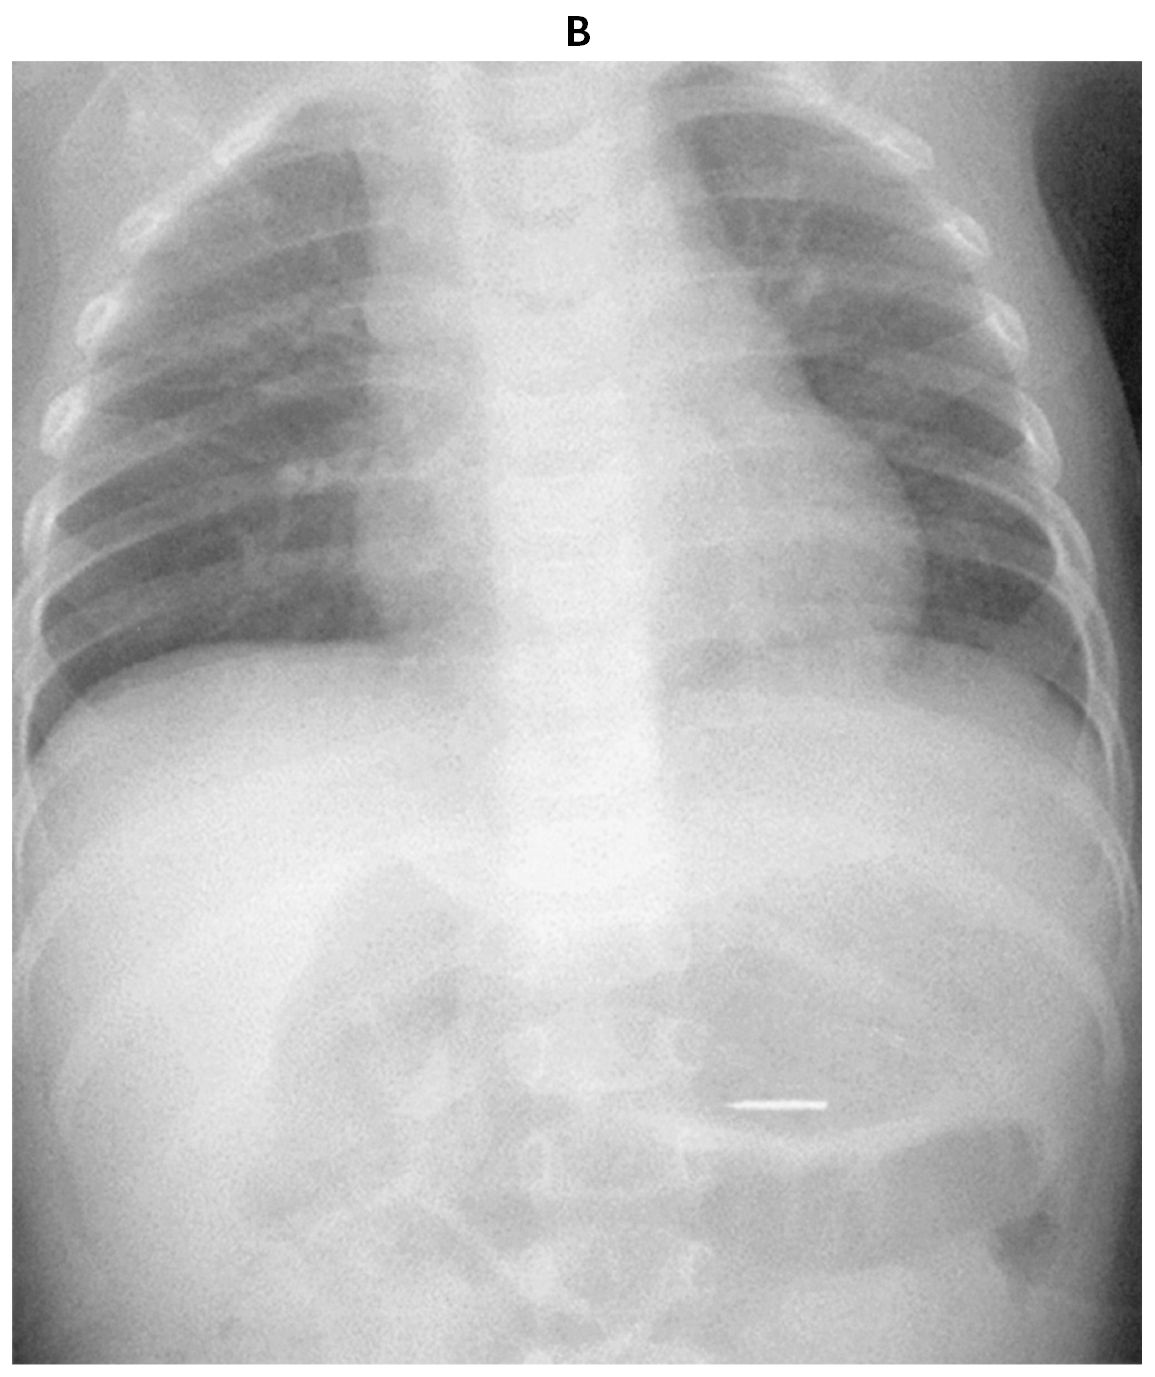

1歳3か月の女児。画鋲を誤飲したため救急車で搬入された。机の上に置いてあった画鋲を飲んだところを母親が目撃し,救急車を要請した。飲み込んだ画鋲と同じものを持参している。体温36.4℃。心拍数110/分,整。血圧84/50mmHg。呼吸数30/分。SpO2 98%(room air)。機嫌はよく,顔色は良好である。努力呼吸を認めず,呼吸音に異常を認めない。腹部を軽く触ると平坦で軟らかく,啼泣は認めない。持参した画鋲の写真(A)と来院時の胸腹部エックス線写真(B)を下に示す。